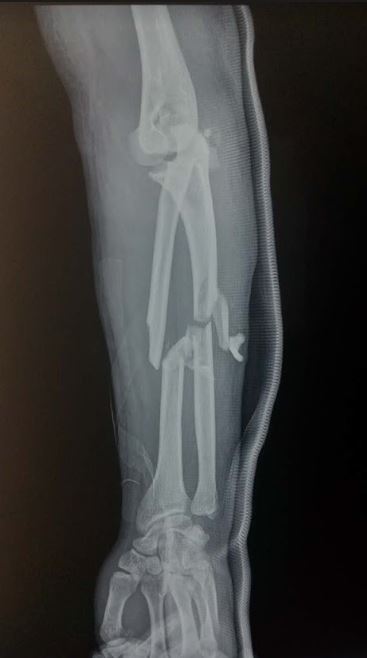

Jabka labada lafood ee u dhaxeeya xusulka iyo gacanta (Forearm fractures) badanaa waxaa keena jug toos ah oo ku dhacda lafta ama ilmaha oo gacanta oo u fidsan dhaca. Hal laf kaliya ayaa jabi karta ama labada lafood ayaa wada jabi kara; jabku wuxuu noqon karaa mid kala bax kala goyska xusulka ama kala goyska gacanta la socdo.

Raajo ayaa lagu xaqiijiyaa jabka; Xalka jabkana wuxuu ku xiran yahay da’da bukaanka iyo nuuca jabka, qaliinkana waxaa la sameeyaa hadii ay jiraan xaaladihii aan kusoo sheegnay qaybta xogta guud. Dhakhtarka ayaa mar kasto talada rasmiga dhiibaayo kadib markuu qiimeeyo xaalka bukaanka iyadoo bukaankuna go’aanka wax ku leeyahay.